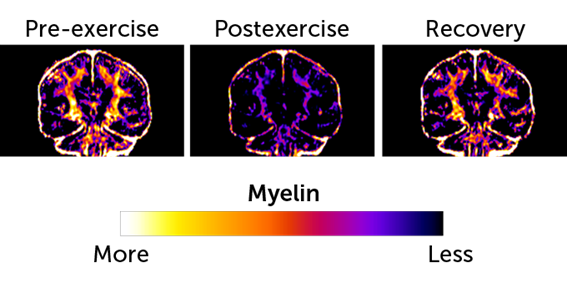

La investigación consistió en escanear cerebros de varios corredores de maratón mediante resonancia magnética durante los días previos y posteriores a la carrera y dos semanas después. Así, descubren que la realización de un maratón reduce el contenido de mielina en gran parte de la sustancia gris y blanca del cerebro. El efecto es similar en ambos hemisferios y es reversible. Es decir, dos semanas después de la finalización del esfuerzo los niveles de mielina fueron casi los mismos. Sin embargo, los investigadores advierten que si el esfuerzo se alargara demasiado, puede tener consecuencias funcionales en el cerebro.

Sin embargo, han llegado a la conclusión de que la mielina puede ser un depósito de energía alternativo que se puede utilizar cuando se reducen los nutrientes que utiliza el cerebro. Es más, señalan que este uso ha abierto una nueva visión de las exigencias energéticas del cerebro, que afecta tanto al rendimiento de los deportistas como a la nutrición de la población general. También han avanzado que puede abrir nuevas líneas de estudio y tratamiento de enfermedades neurodegenerativas, como la esclerosis múltiple y otras enfermedades desmielinizantes.